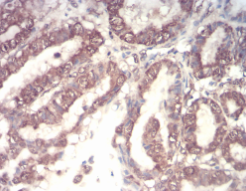

IHC    1/200 - 1/1000